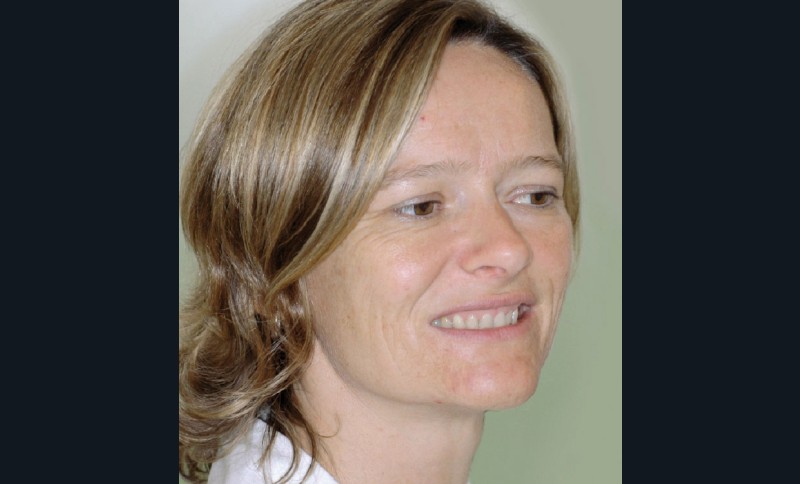

Cette patiente âgée de 39 ans, désireuse d’améliorer son sourire et son confort articulaire mandibulaire, nous est adressée par son chirurgien-dentiste le Dr S. Felenc. En effet, ce dernier ne peut proposer une réhabilitation cosmétique du guide incisivo-canin fonctionnelle, pérenne et non mutilante, sans orthodontie. Comme il l’explique dans une précédente publication, sur cette situation clinique, la phase prothétique doit être aussi économe que possible du point de vue tissulaire (1). Et ici, le faible espace prothétique disponible lié à la classe II division 2, la forte abrasion et la faiblesse amélodentinaire sont associés à un désordre plus global des bases osseuses.

Le préjudice esthétique vient de la concavité du profil accentuée par la profondeur nasale, l’ouverture de l’angle naso-labial et la proéminence du menton. Les lèvres sont fines et tendues. L’inclinaison vestibulo-linguale, le recul et la petitesse des dents ne soutiennent pas les lèvres lors du sourire de profil. De plus, le sourire est gingival et laisse apparaître le torque radiculo-vestibulaire excessif des incisives et des canines maxillaires, d’où leur peu d’éclat, aggravé par des restaurations au composite (fig. 1a-c et 2).